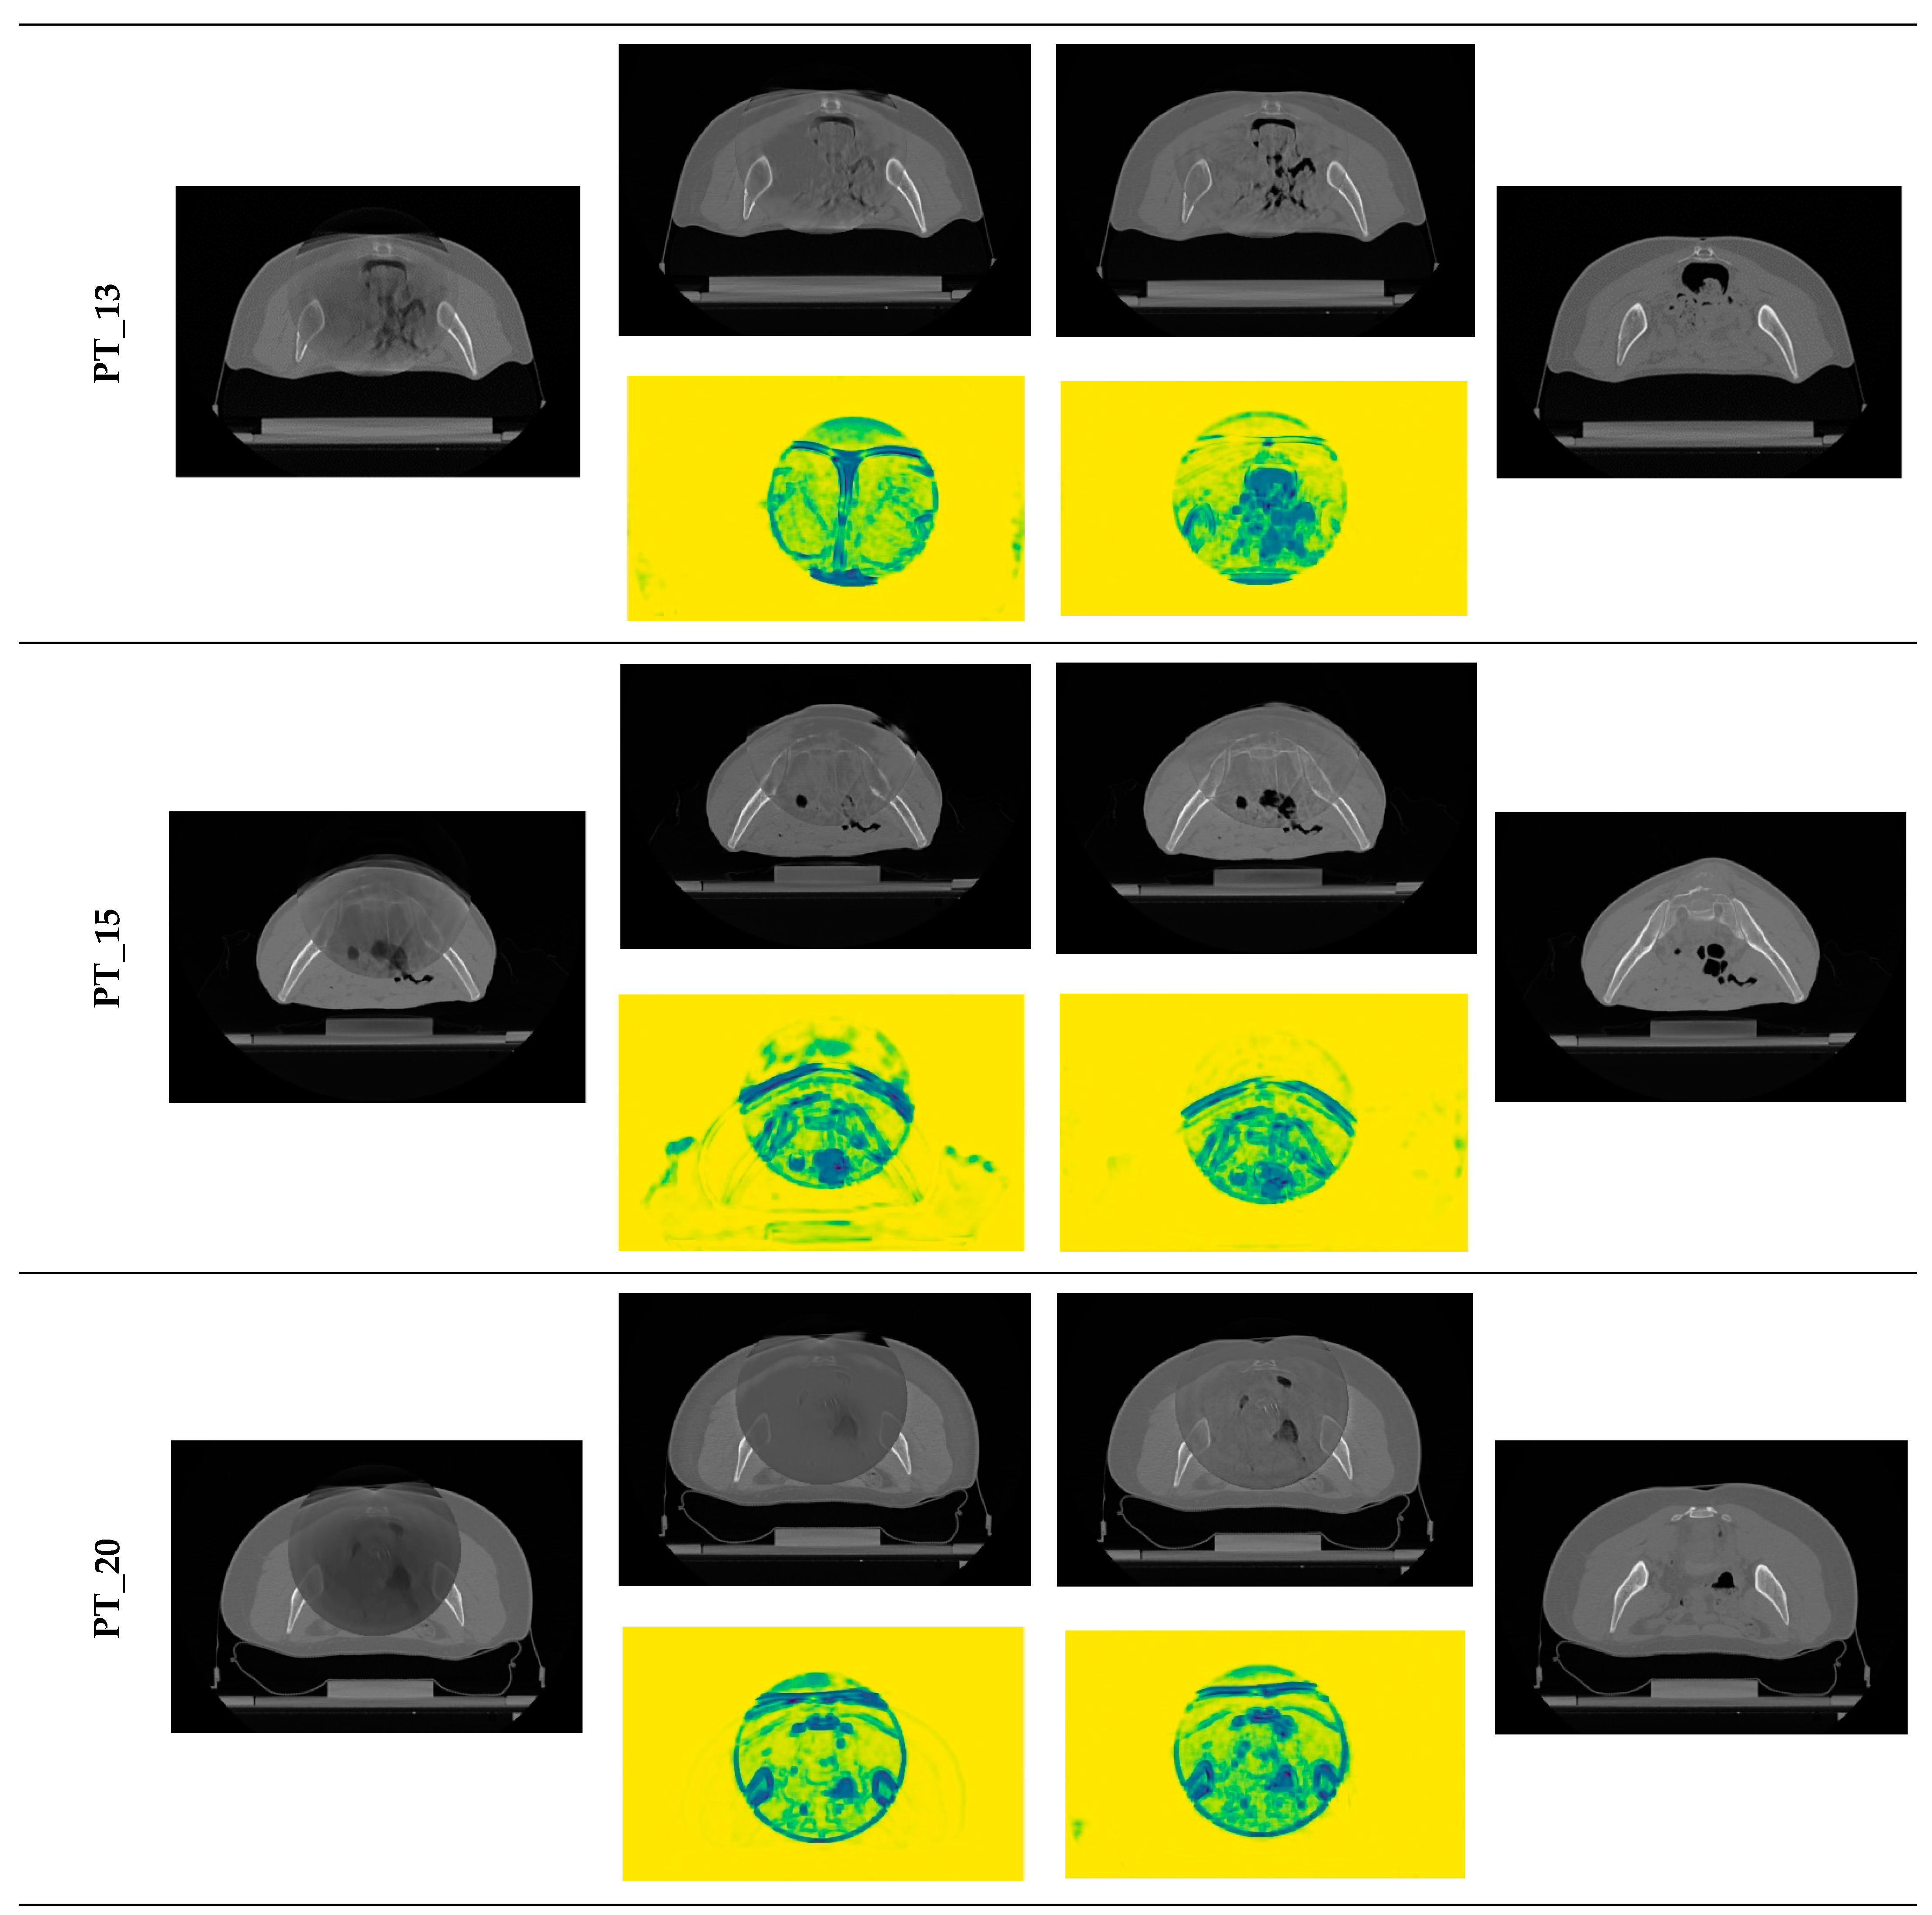

3.4. Qualitative Evaluation

| PT_13 | Pre | 0.75, 0.04 | 48.66, 2.19 | 0.75, 0.04 | 48.66, 2.19 | |

| Post | 0.83, 0.02 | 52.96, 3.47 | 0.78, 0.04 | 50.73, 2.34 | ||

| p-value | <0.05 | <0.05 | <0.05 | <0.05 | ||

| PT_15 | Pre | 0.75, 0.03 | 48.24, 2.14 | 0.75, 0.03 | 48.24, 2.14 | |

| Post | 0.80, 0.03 | 52.95, 3.02 | 0.78, 0.05 | 50.48, 1.60 | ||

| PT_20 | Pre | 0.68, 0.07 | 44.40, 2.10 | 0.68, 0.07 | 44.40, 2.10 | |

| Post | 0.73, 0.08 | 48.98, 2.89 | 0.73, 0.06 | 48.17, 2.05 | ||